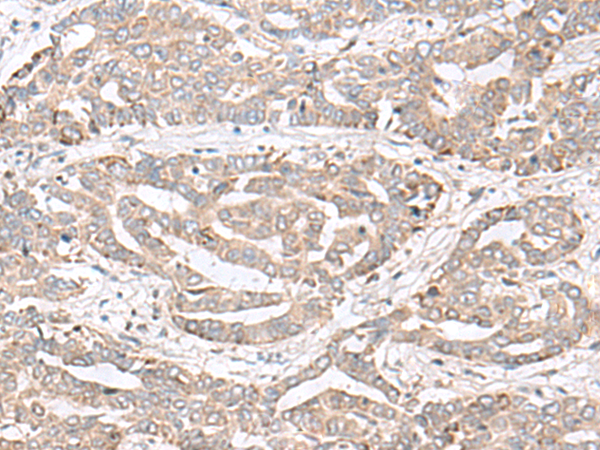

分类: 科研抗体货号: P06532别名: FNIPL; MAPO1应用: IHC反应种属: Human